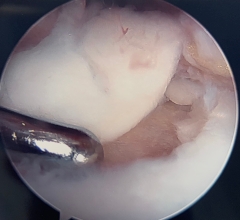

Arthroscopic view of large talar chondral lesion